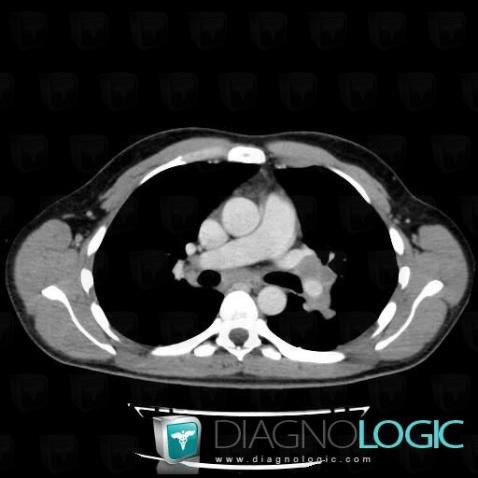

Voici les informations spécifiques à l'image clé ci dessus:

- Diagnostic Lymphome , Localisation(s) Médiastin, comportant les gammes Adénomégalie hilaire